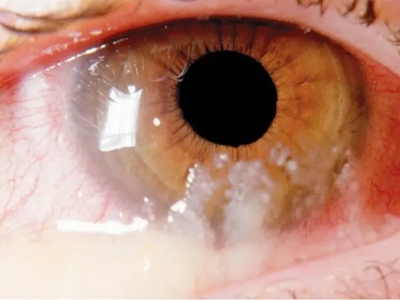

急性或亚急性细菌性结膜炎俗称“红眼病”,多见于春秋季节,可散发感染,也可流行于学校、工厂等集体生活场所。发病急,潜伏期1-3日,两眼同时或相隔1-2日发病。发病3-4日时病情达到高潮,以后逐渐减轻。临床上主要表现为显著的结膜充血、黏液或黏脓性结膜分泌物。

急性或亚急性细菌性结膜炎患者自觉流泪、异物感、灼热感或刺痛等。由于分泌物多,常使上、下睫毛粘在一起,早晨起床时睁眼困难,并且眼睑肿胀,结膜充血,结膜表面有分泌物。分泌物先为黏液性,而后呈脓性。严重时结膜表面可覆盖一层假膜。

偶可并发卡他性边缘性角膜浸润或溃疡(多见于流感嗜血杆菌型感染)。 Koch-Weeks杆菌或肺炎双球菌性结膜炎患者一般为双侧性,结膜高度充血和水肿,可发生结膜下出血斑点,常伴有体温升高、身体不适等全身症状。